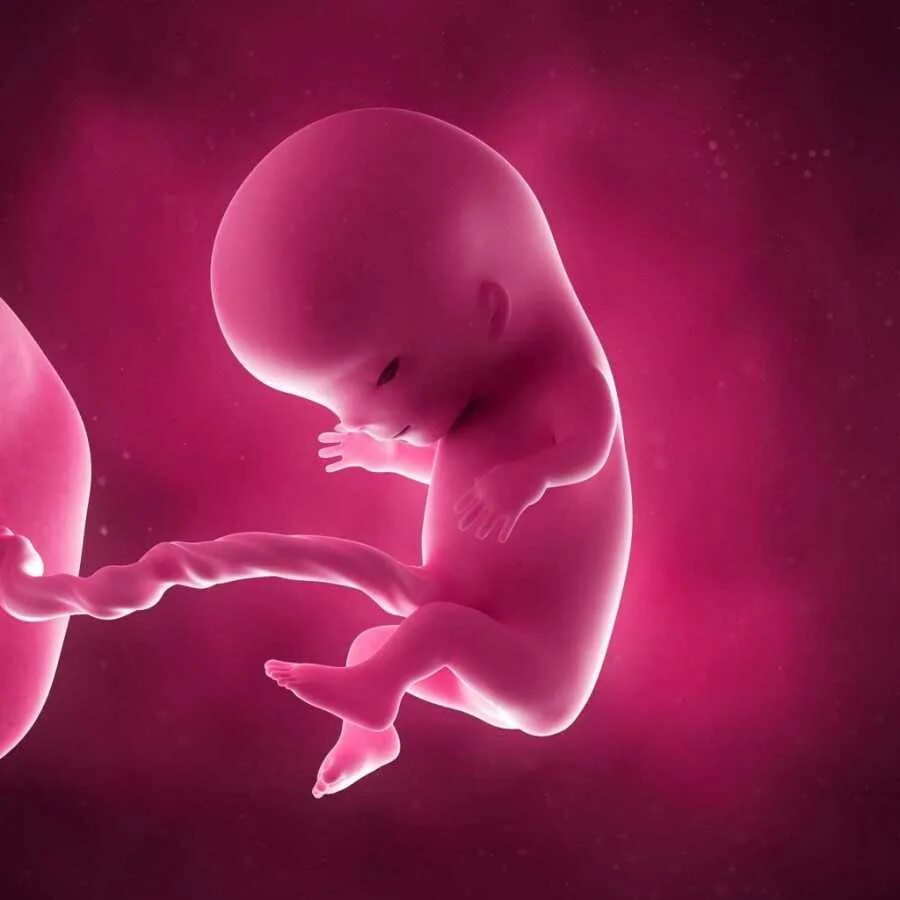

Ребенок в утробе 31 неделя